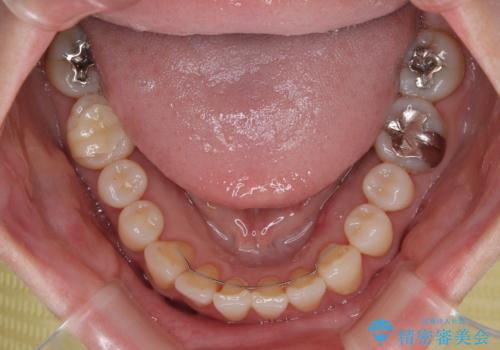

前歯のデコボコをインビザライン・モデレートで矯正治療

- 上下前歯のデコボコを気にして来院された患者様です。

安価なインビザラインパッケージを用いての治療を希望されており、デコボコの程度が中等度であったため、インビザライン・モデレートを用いて矯正治療を行うこととしました。

インビザライン・モデレートは、製作できるアライナーの枚数に制限があるため、移動可能な量に限りがあるものの、インビザライン・ライトよりも枚数が多いため、幅広い症例に対応可能です。